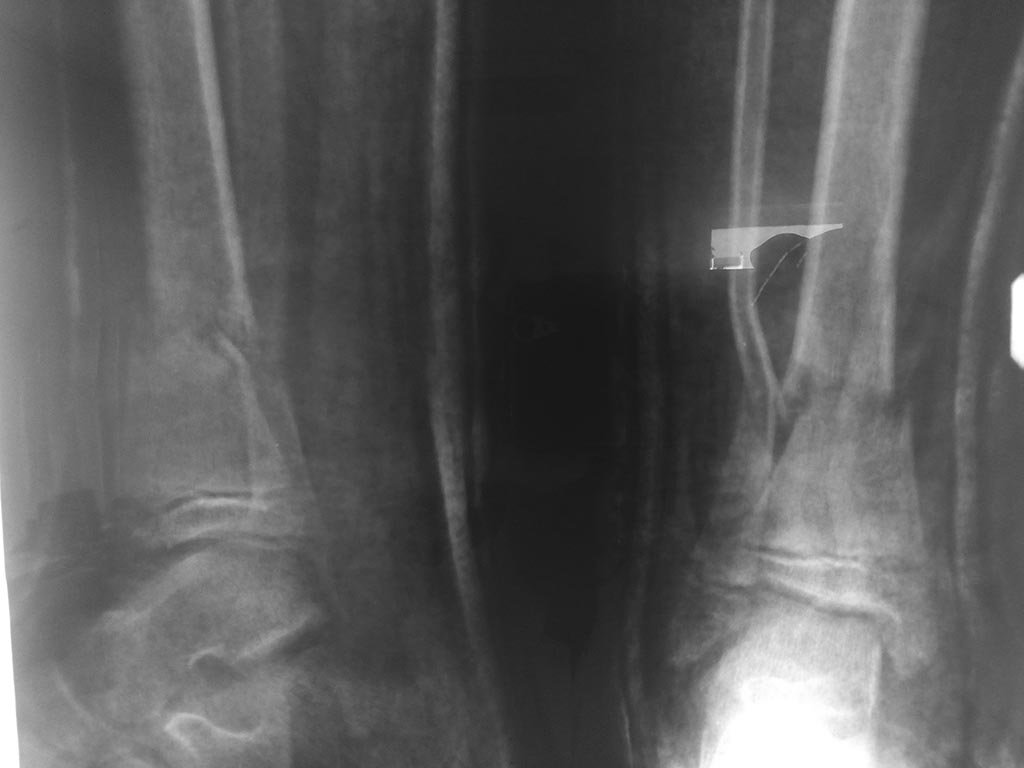

[Ortho] Перелом у ребенка 2006г

Допустимо ли стояние отломков касательно ребенка 2006г.